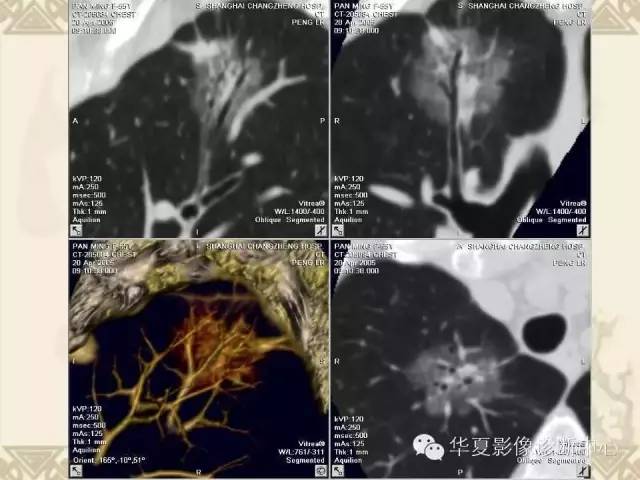

肺内磨玻璃样结节的影像诊断与处理对策